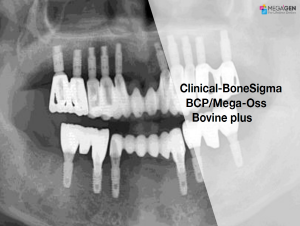

Aesthetic zone,AnyRidge,Clinical case,Dr. Achraf Souayah,Edentulous,Guided surgery,Immediate Placement,Mandibular Anterior,Mandibular Posterior,Maxillary Anterior,Maxillary Posterior,MEG-Rhein,MILA Kit,Overdenture system,Sinus Elevation